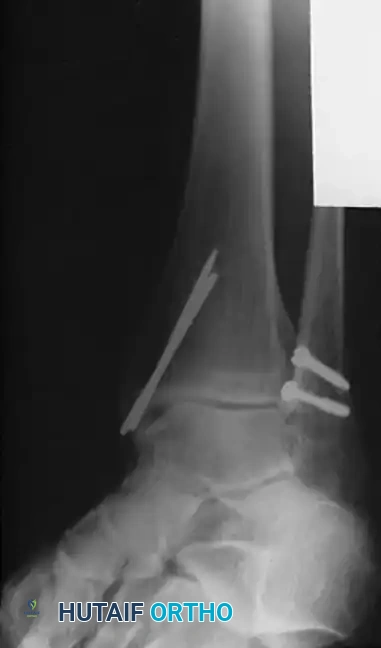

Image

FIGURE 54-4: Fracture of the fibula above the level of the syndesmosis with disruption of the distal tibiofibular syndesmosis and rupture of the deltoid ligament. The deltoid was repaired, a small fragment plate was applied to the fibula, and the syndesmosis was repositioned and held by a transfixing screw through the distal hole of the fibular plate.